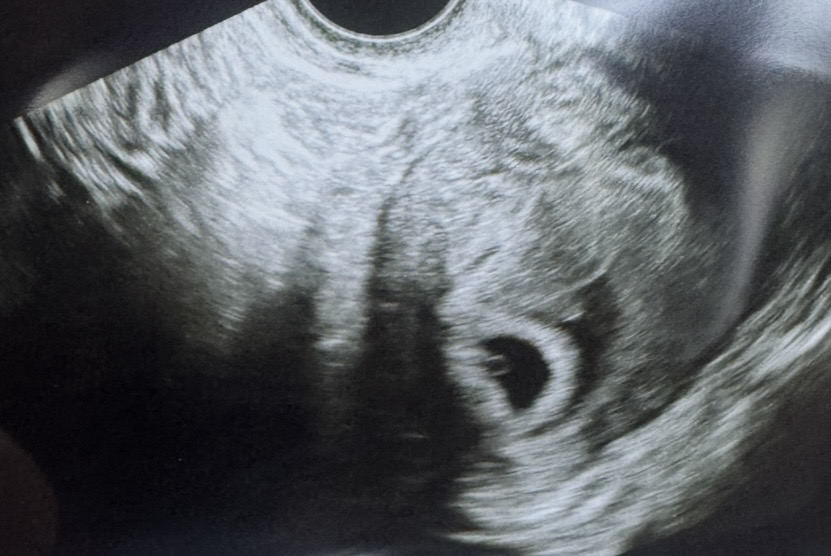

막생기준 5월 9일, 아기집이랑 난황보고 왔어요

막생기준 5월 9일, 아기집이랑 난황보고 왔어요 아기집만 볼줄 알았는데 난황도 봤어요 임신확인서 써주셨고 2주 뒤 7주때 오라고 하셨어요~ 자연임신 주기28일 배란일 5월17일 입니다 피고임도 있다고 하셨는데 자연배출되거나 흡수될거라고 하셨어요(그래도 걱정이네여 ㅠ)